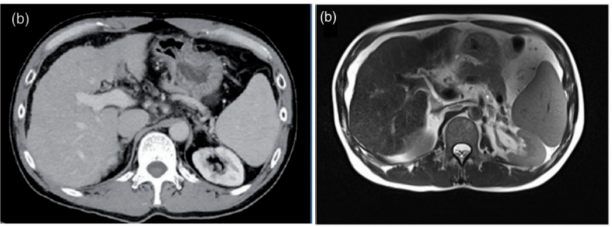

患者男性,65岁(体重61公斤),诊断为晚期HCC。CT和MRI显示原发性肝脏肿瘤伴多发肝转移及门静脉浸润。血清AFP和PIVKA-II水平显著升高,高度提示晚期HCC。

他接受相同的治疗方案,并在6个月后根据PET-CT扫描达到CR。然而,该患者并没有进行手术来确认肿瘤细胞是否消失。目前,该患者已存活24个月以上,无任何症状。监测了两例患者的不良反应,没有证据表明联合治疗的副作用增加。